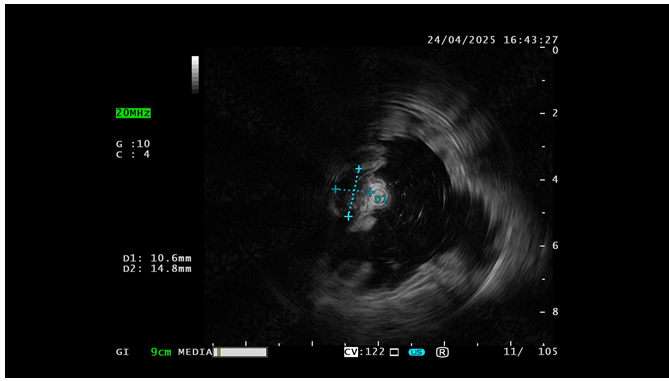

门诊胃镜检查发现:在胃体上部大弯侧见一黏膜下隆起,表面光滑,直径约1.2 cm,活检钳触之有黏膜下滑动感,考虑间质瘤可能。入院后完善超声内镜检查提示:胃体上部大弯见一低回声病变,切面大小1.1×1.5 cm,边界清晰,内部回声均匀,向腔内外突出,起源于固有肌层,结合中国消化道黏膜下肿瘤内镜诊治专家共识指南,该患者有内镜治疗适应证,无禁忌证,交代手术治疗方案选择及手术风险后进行内镜下治疗。

image.png